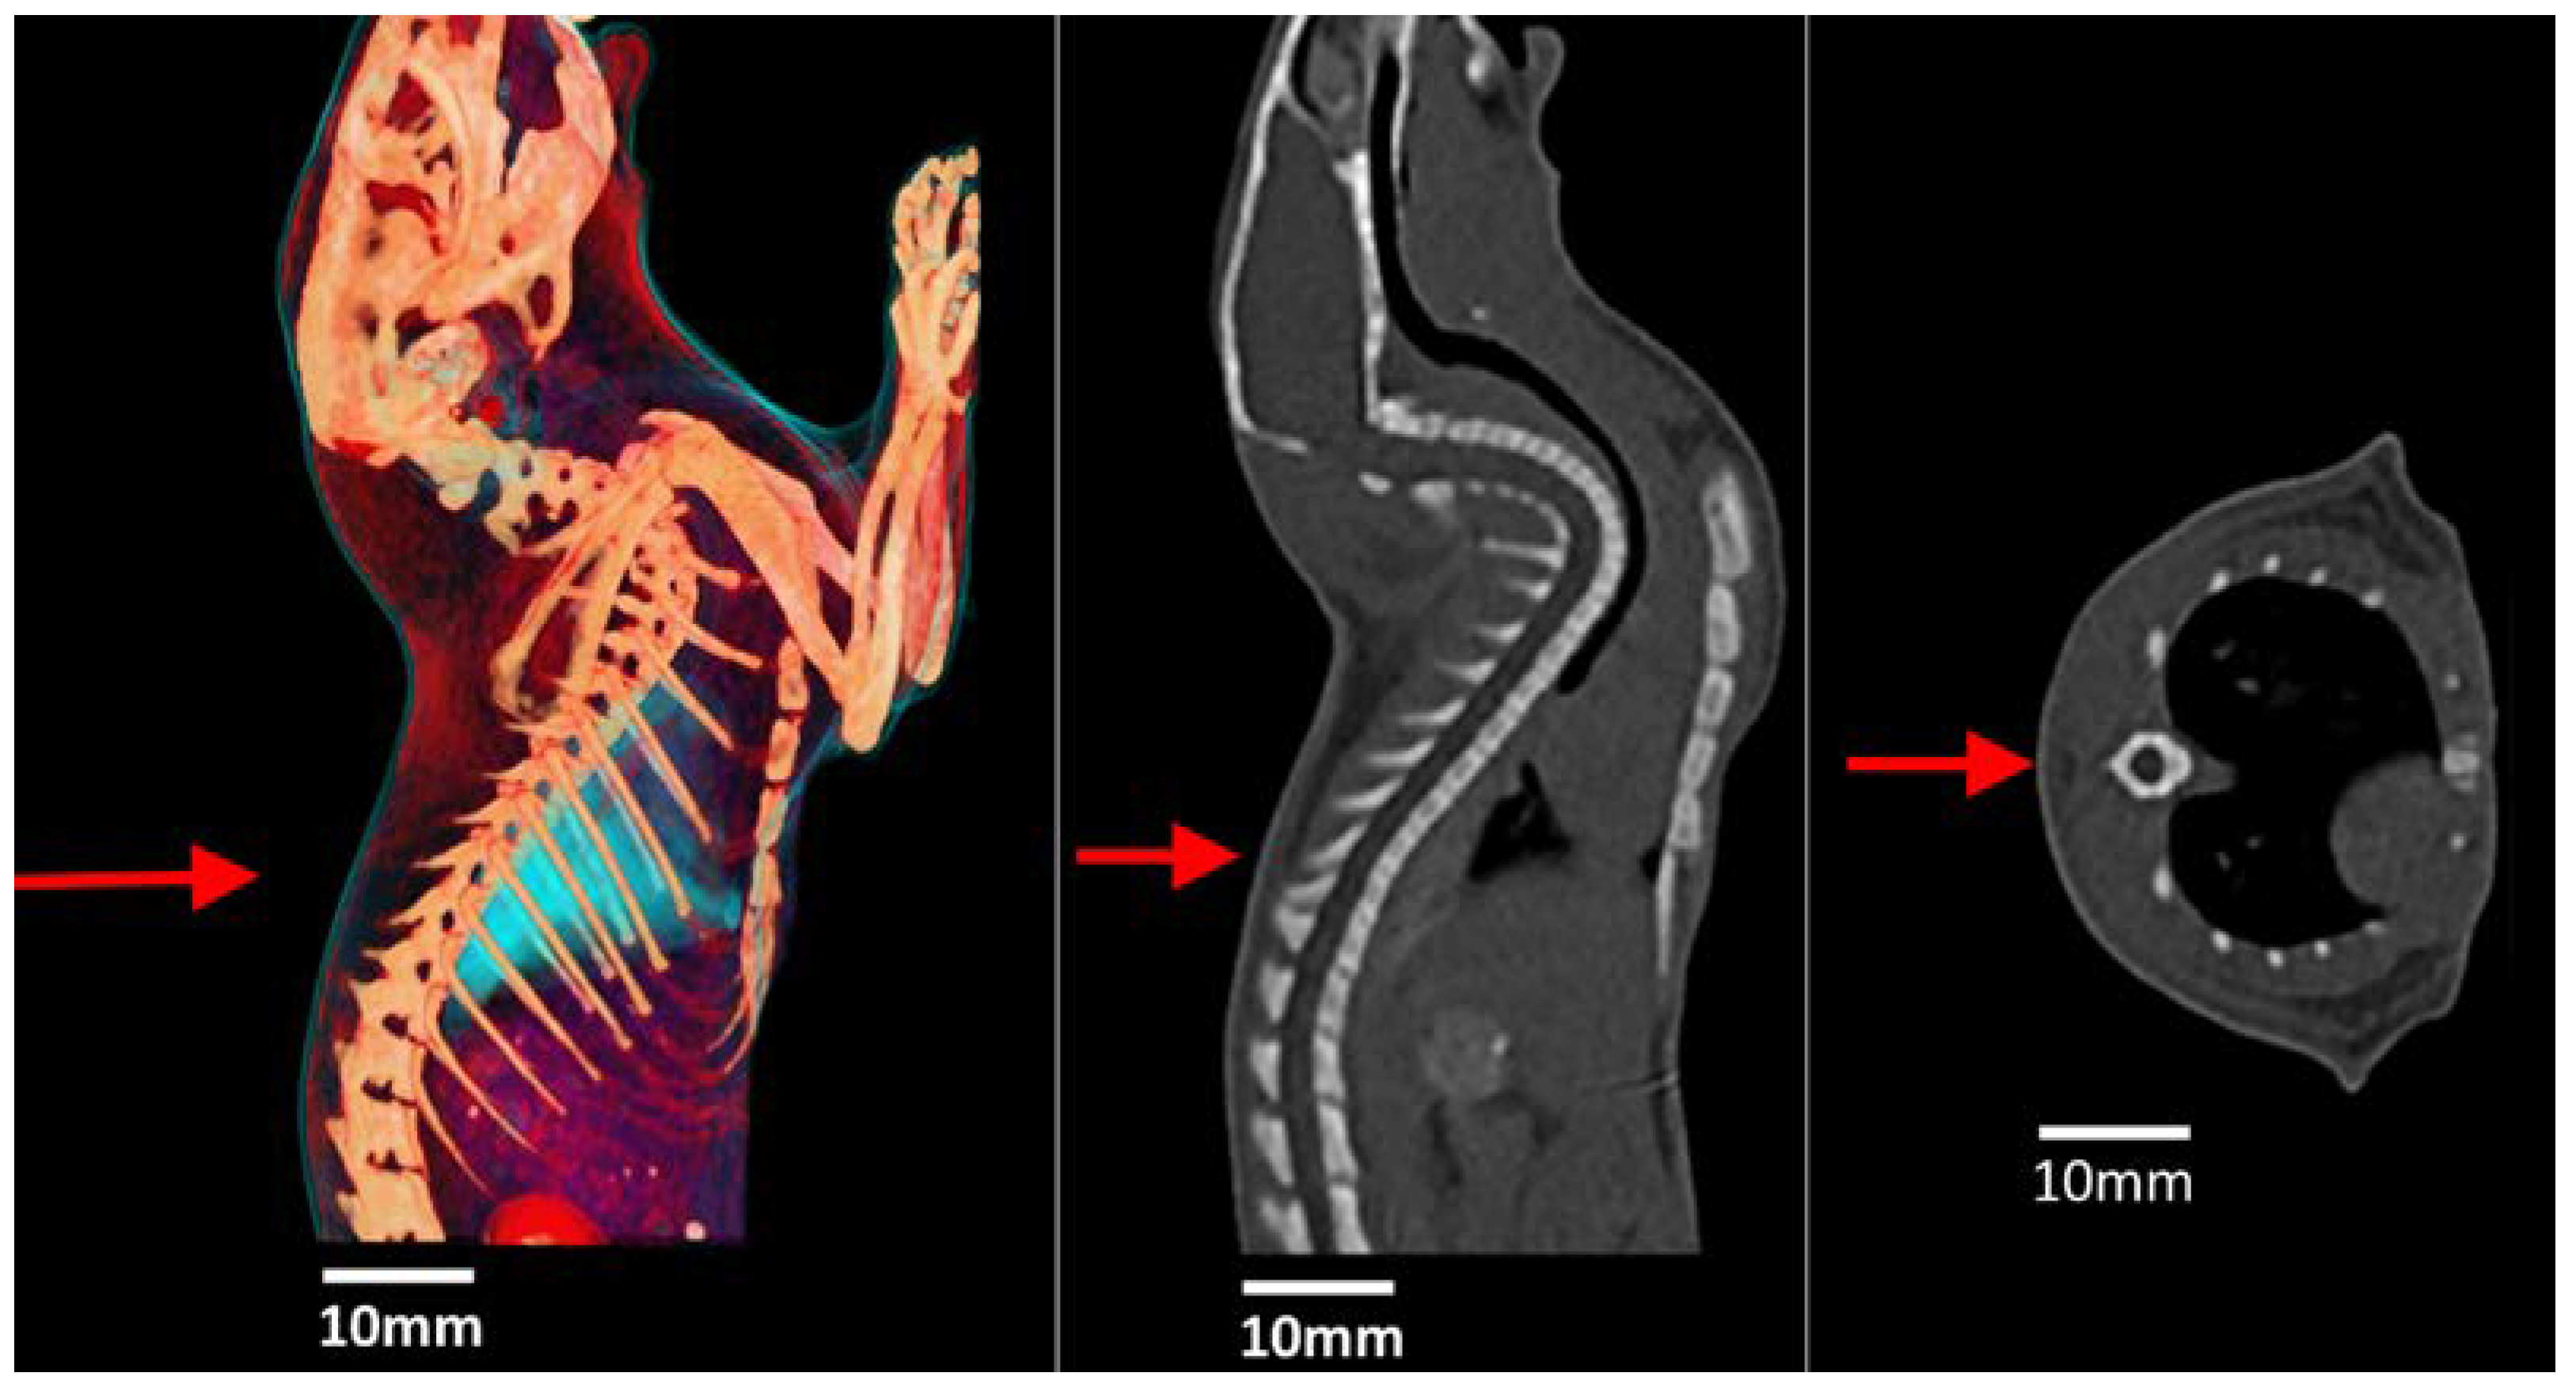

3.5. Post-Mortem MRI